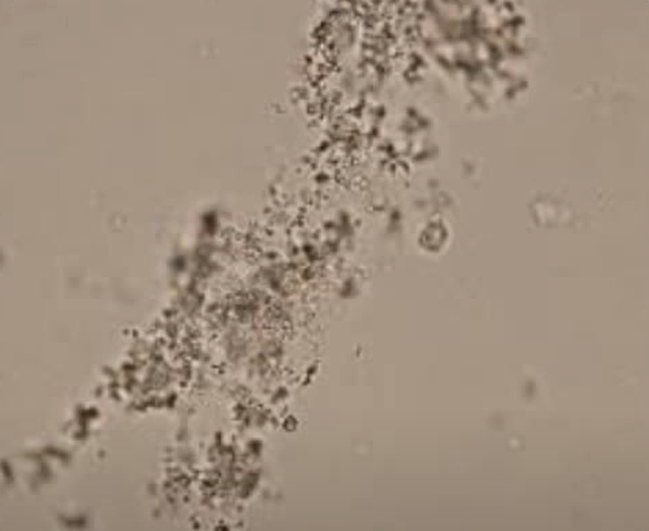

Cristais amorfos